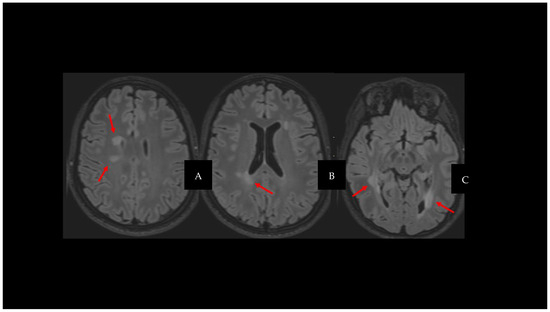

2. Cortical Lesions

3. Iron-Derived Imaging and Chronic Inflammation